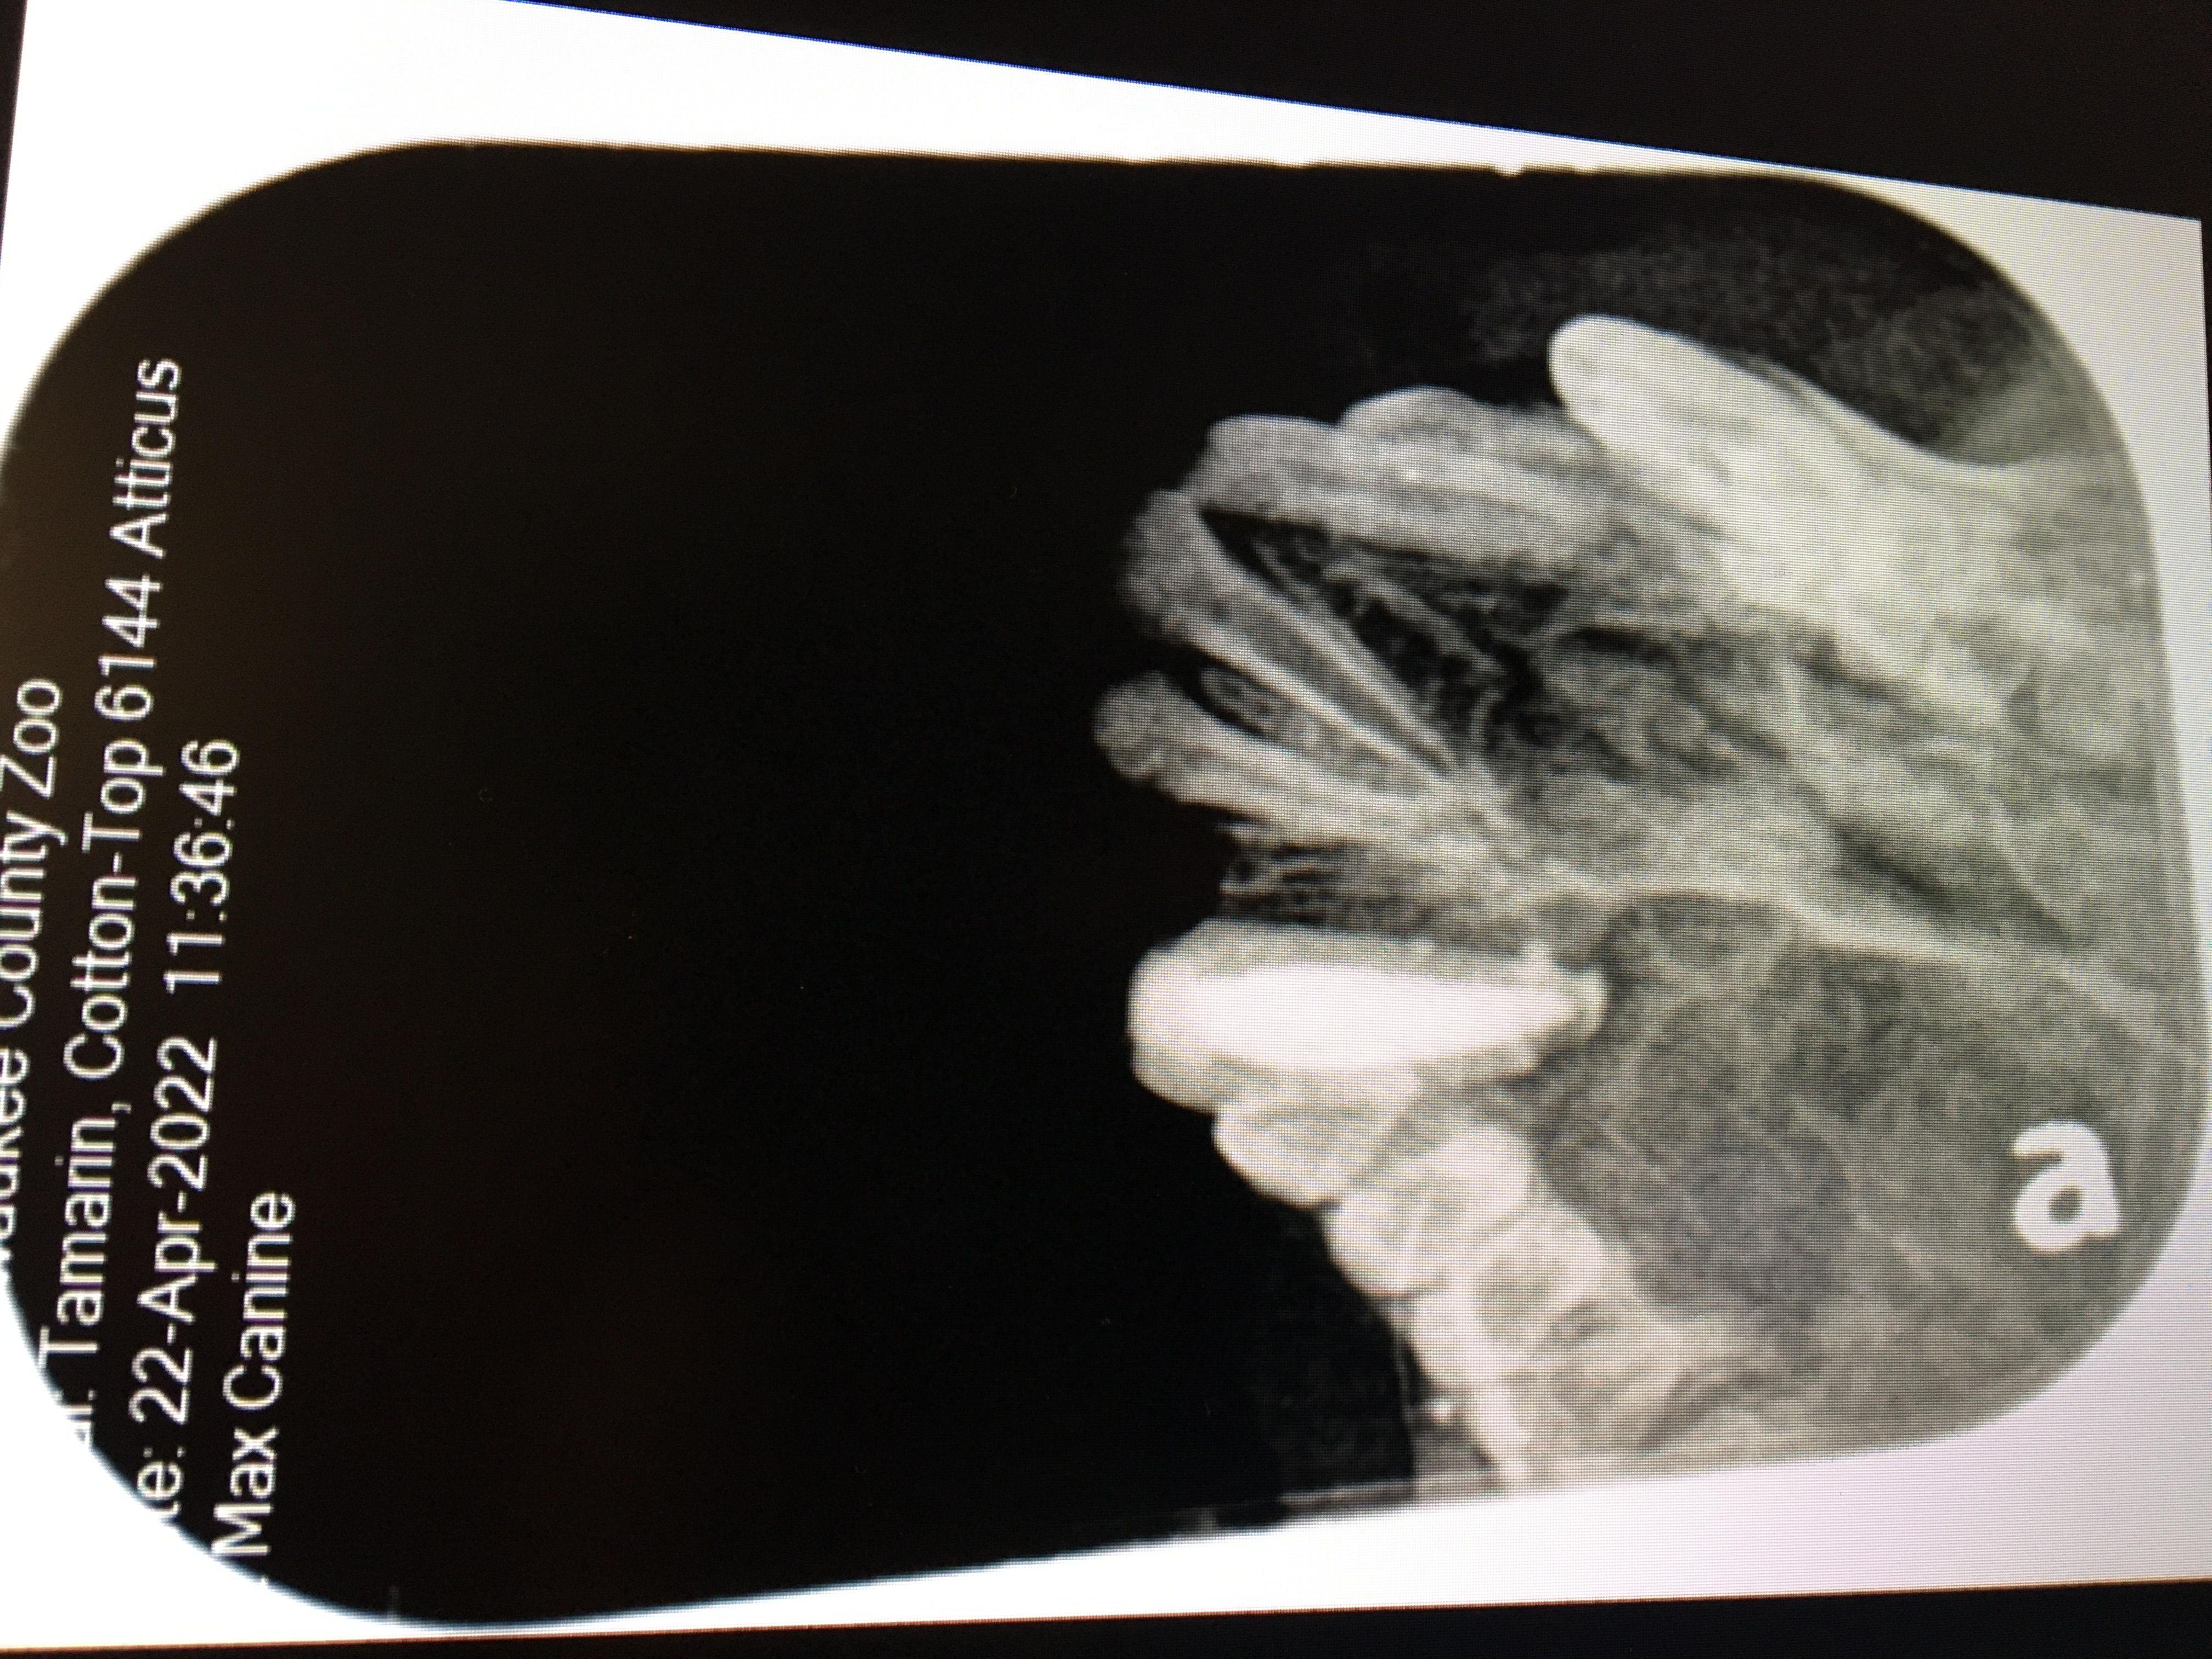

A 2022 Cotton Top Tamarin maxillary canine endodontic procedure is an example of successful endo case that avoided a surgical extraction for this very small patient. A working length radiograph revealed with file in place at 11 mm. showed that the file had gone beyond the apex. 8mm. was chosen as the proper working length and the endo procedure was completed. See fill radiograph.

Cotton top tamarin